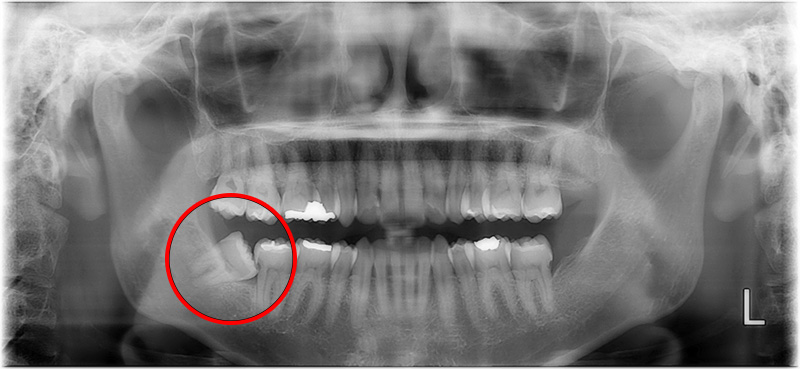

before

| ■性別・年代 | 女性・40代 |

|---|---|

| ■治療内容 | 汚れが溜まり虫歯があり右下の親知らずを抜歯しました。 |

| ■金額 | 埋伏抜歯 5,120円 CT 4,400円 |

| ■治療期間 | 1日 |

| ■通院回数 | 1回 |

| ■リスク・副作用 | 抜歯後にしびれが出ることや、まれに腫れや痛みが長引くことがあります。 |